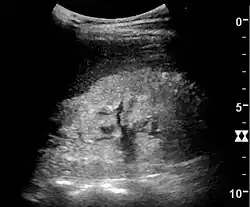

Ultrasound

Kidney ultrasonography is useful for diagnostic and prognostic purposes in chronic kidney disease. Whether the underlying pathologic change is glomerular sclerosis, tubular atrophy, interstitial fibrosis, or inflammation, the result is often increased echogenicity of the cortex. The echogenicity of the kidney should be related to the echogenicity of the liver or the spleen. Moreover, decreased kidney size and cortical thinning are often seen, especially when the disease progresses. However, kidney size correlates to height, and short persons tend to have small kidneys; thus, kidney size as the only parameter is unreliable.[63]

Chronic renal disease caused by glomerulonephritis with increased echogenicity and reduced cortical thickness. Measurement of kidney length on the US image is illustrated by '+' and a dashed line.[63] -